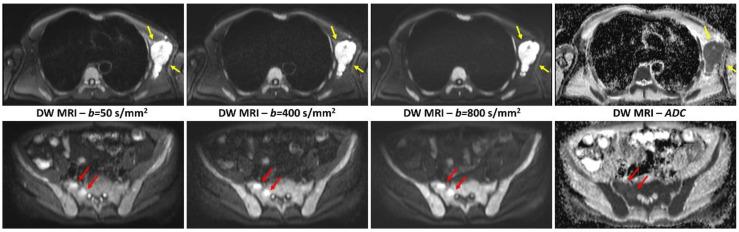

Bone disease is one of the major features of multiple myeloma (MM), and imaging has a pivotal role in both diagnosis and follow-up. Whole-body magnetic resonance imaging (MRI) is recognized as the gold standard for the detection of bone marrow involvement, owing to its high sensitivity. The use of functional MRI sequences further improved the performances of whole-body MRI in the setting of MM. Whole-body diffusion-weighted (DW) MRI is the most attractive functional technique and its systematic implementation in general clinical practice is now recommended by the International Myeloma Working Group. Whole-body dynamic contrast-enhanced (DCE) MRI might provide further information on lesions vascularity and help evaluate response to treatment. Whole Body PET/MRI is an emerging hybrid imaging technique that offers the opportunity to combine information on morphology, fat content of bone marrow, bone marrow cellularity and vascularization, and metabolic activity. Whole-body PET/MRI allows a one-stop-shop examination, including the most sensitive technique for detecting bone marrow involvement, and the most recognized technique for treatment response evaluation. This review aims at providing an overview on the value of whole-body MRI, including DW and DCE MRI, and combined whole-body F-FDG PET/MRI in diagnosis, staging, and response evaluation in patients with MM.